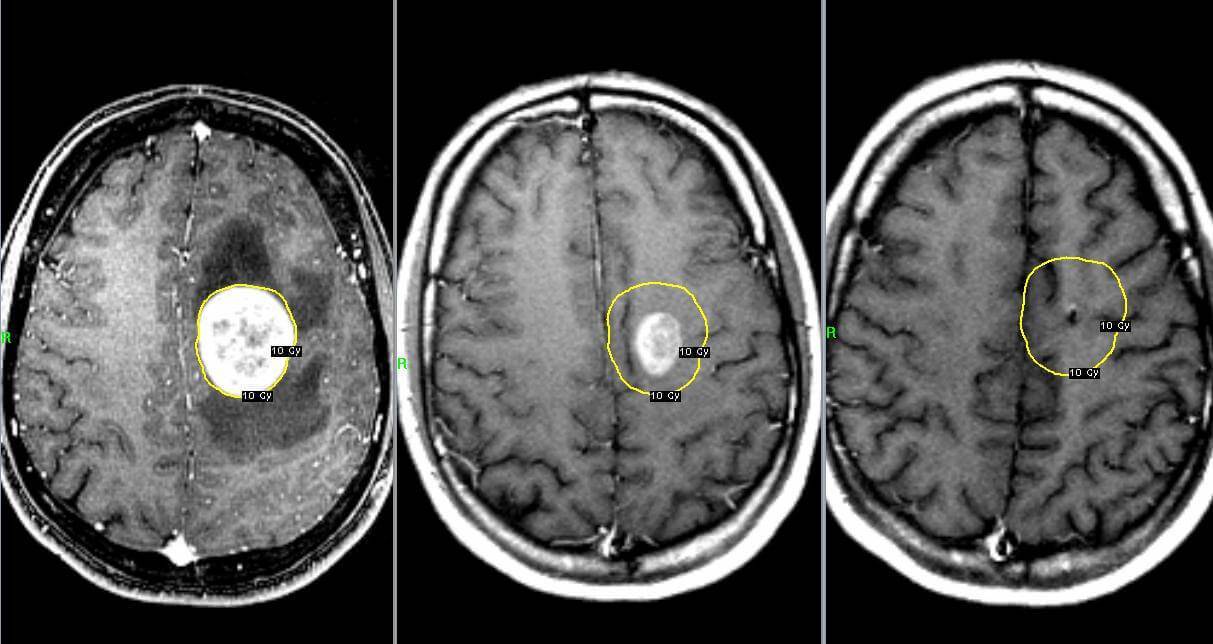

Стереотаксическая радиохирургия является новейшим способом лечения опухолей ствола. Можно проводить два вида радиохирургии:

- гамма-нож — больному надевают на голову специальный шлем для облучения из множества точек. Лучи сводятся в одной точке, где локализуется опухолевый очаг. Здоровые ткани при таком воздействии практически не страдают. Каждые луч имеет небольшое количество гамма-энергии, но суммарное влияние всех лучей способствует достижению максимального эффекта.

- кибер-нож — выполняется с помощью робота и является автоматизированной процедурой. Аппарат самостоятельно концентрирует излучение в область расположения новообразования. Движения пациента и дыхание не дают возможности сбиться в наведении пучка лучей.

Исследования доказывают состоятельность этих методов при лечении доброкачественных новообразований, величиной до 3,5 см.

- Радиохирургия. Она относится к разновидностям облучения. В рамках процедуры пациент проходит небольшие дозы облучения с разных сторон, при этом лучи сходятся в месте локализации новообразования, уничтожая его. При этом окружающие ткани остаются невредимыми.

Роботизированная радиохирургия на системе «Кибер Нож»

Эта технология является разновидностью дистанционной лучевой терапии, но она позволяет настолько точно подвести дозу к патологическому очагу и воздействовать на него с точностью до миллиметра, что ее называют радиохирургией. Она может проводиться не только на линейном ускорителе электронов КиберНож, но и на других современных ускорителях, более универсальных, и на аппарате ГаммаНож. Технически это реализуется следующим образом — опухоль облучается со многих направлений малыми дозами, которые, по отдельности проходя сквозь здоровые ткани, практически не влияют на них. Но пучки ионизирующего излучения, сходясь в одном объёме, образуют в нём высокую дозу облучения, что приводит к уничтожению в этом объёме опухолевой ткани. Таким образом достигается лечебный эффект. Метод позволяет прицельно облучать небольшие опухоли, расположенные в труднодоступных для хирургии местах.